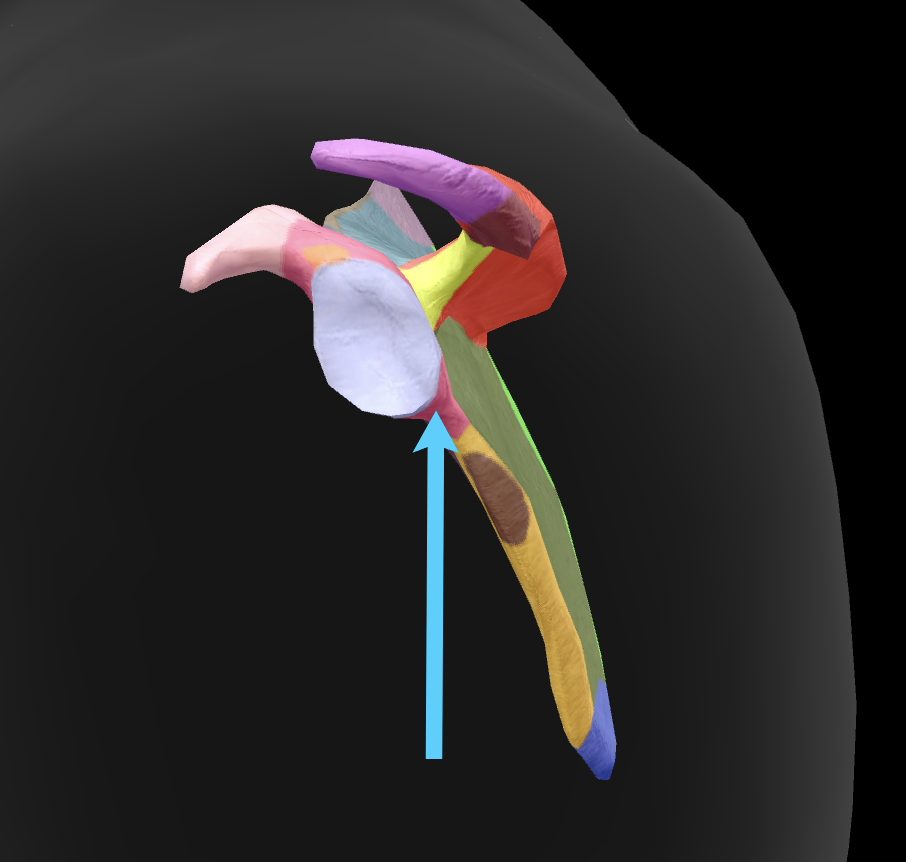

scapula

What is this boney landmark?

spine of scapula

What is this boney landmark?

supraspinous fossa

What is this boney landmark?

infraspinous fossa

What is this boney landmark?

acromion process

What is this boney landmark?

superior angle

What is this boney landmark?

inferior angle

What is this boney landmark?

lateral border

What is this boney landmark?

medial border

What is this boney landmark?

subscapular fossa

What is this boney landmark?

spinoglenoid notch

What is this boney landmark?

glenoid fossa

What is this boney landmark?

supraglenoid tubercle

What is this boney landmark?

infraglenoid tubercle

What is this boney landmark?

coracoid process

What bone is this?

humerus

What is this boney landmark?

head

What is this boney landmark?

anatomical neck

What is this boney landmark?

surgical neck

What is this boney landmark?

lesser tubercle

What is this boney landmark?

bicipital grove

What is this boney landmark?

deltoid tuberosity

What is this boney landmark?

shaft

What is this boney landmark?

capitulum

What is this boney landmark?

trochlea

What is this boney landmark?

radial fossa

What is this boney landmark?

coronoid fossa

What is this boney landmark?

medial epicondyle

What is this boney landmark?

lateral epicondyle

What is this boney landmark?

greater tubercle